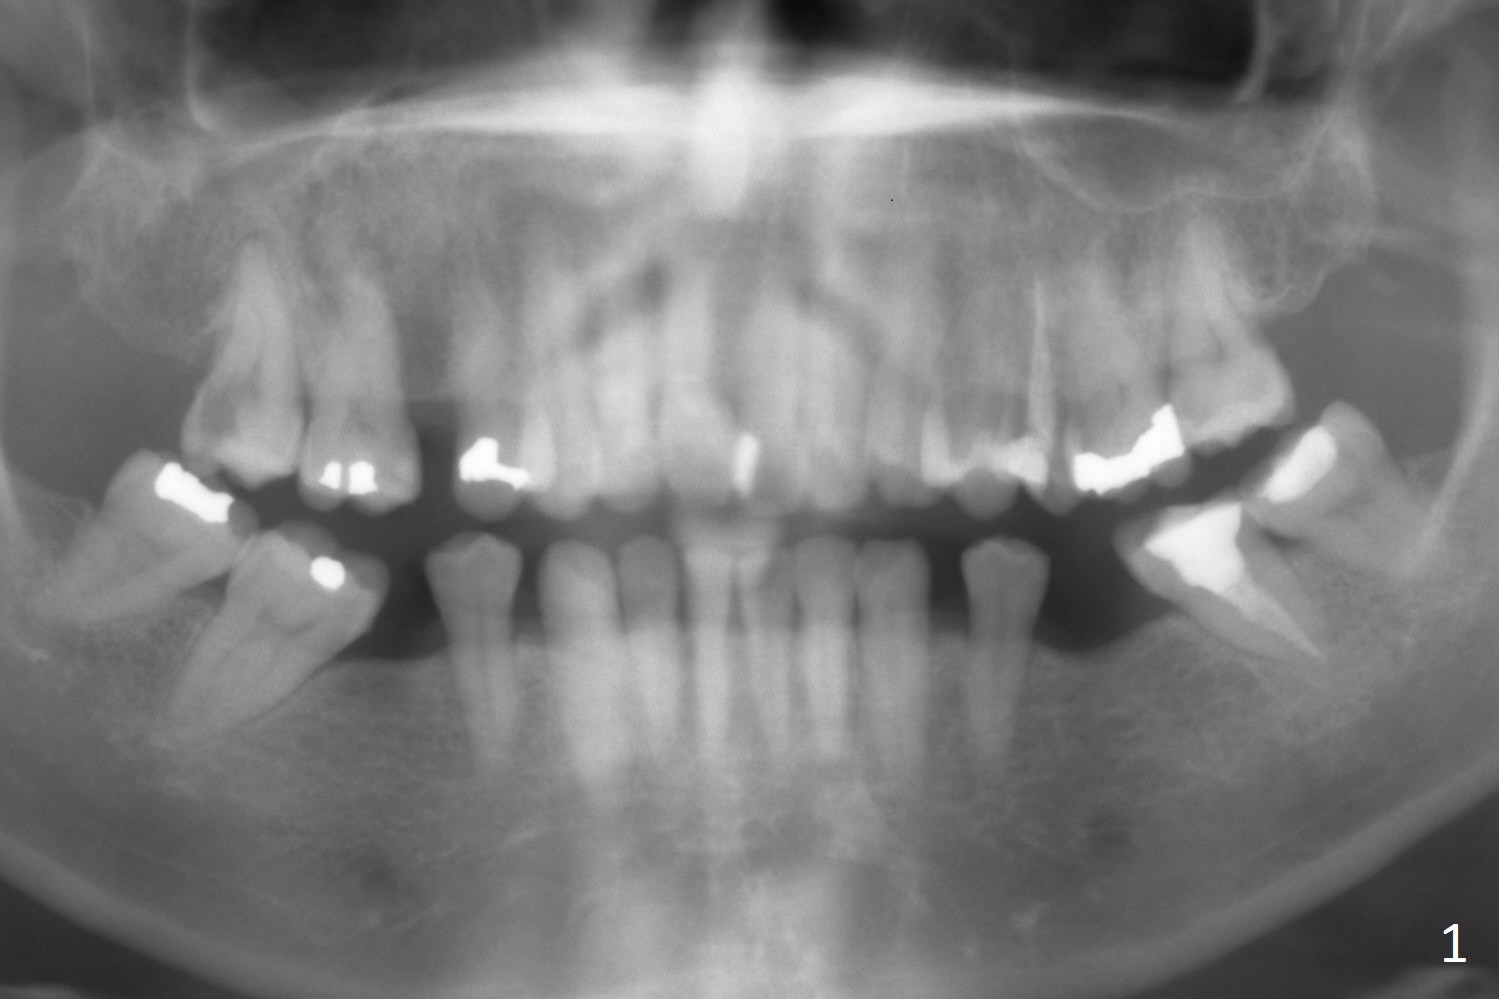

A 51-year-old woman requests extraction of the upper right 2nd molar (Fig.1) with caries and sensitivity (Fig.2 *). After discussion of treatment options including RCT, she chooses implant. The tooth has most likely fused roots and single socket. Try to use tap drills to form osteotomy palatal and deep.

In fact the patient is unwilling for immediate implant. Instead socket preservation is performed with allograft/Osteogen and Osteogen plug.